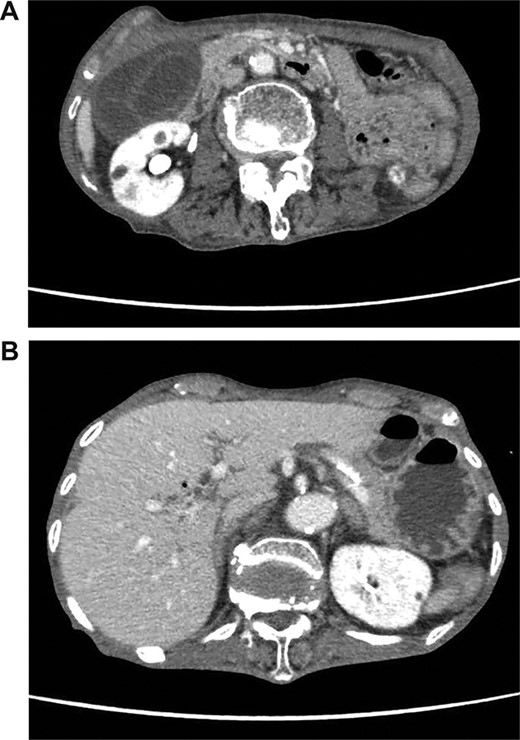

We found a gangrenous gallbladder with 180° clockwise rotation along the longitudinal axis and performed cholecystectomy (Fig. 3). Intraoperative exploration revealed no ischemic findings in other visceral organs. On US obtained immediately after the operation, the hyperechogenic foci disappeared (Fig. 4). Her postoperative course was uneventful, and she was transferred to the rehabilitation hospital on the 12th day. Histology confirmed a necrotic gallbladder without neoplastic changes.

Ultrasonography after surgery shows no findings of PVG in the liver.